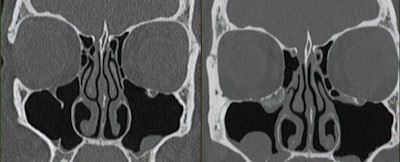

47-year-old’s sinuses evaluation using both energy-integrating detector (EID), left, and PCCT, right, scanners. Coronal images are shown. PCCT examination included additional dose reduction methods including tin filtration and ultrahigh-resolution acquisition. Volume computed tomography dose index is lower for PCCT than for EID scanner (9 vs 26 mGy, respectively); yet, PCCT image has less noise. EID CT examination was performed on Siemens Sensation 64 scanner with following parameters: detector configuration, 32x0.6 mm; z-flying focal spot (64x0.6 mm); tube potential, 120 kV; rotation time, 1 second; helical pitch, 0.9; effective mAs, 170; kernel, H70; slice thickness, 0.75 mm; matrix, 512. PCCT examination was performed on Siemens NAEOTOM Alpha scanner with following parameters: detector configuration, 120x0.2 mm; tube voltage, 100 kV with added tin filter; rotation time, 1 second; helical pitch, 0.85; kernel, Hr72 with QIR strength setting of 3; slice thickness, 0.6; mm; matrix, 1024.American Journal of Roentgenology